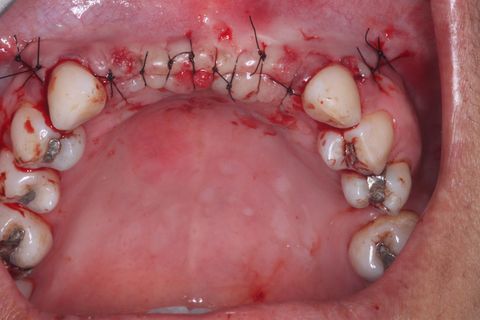

Sutura

Sutura final